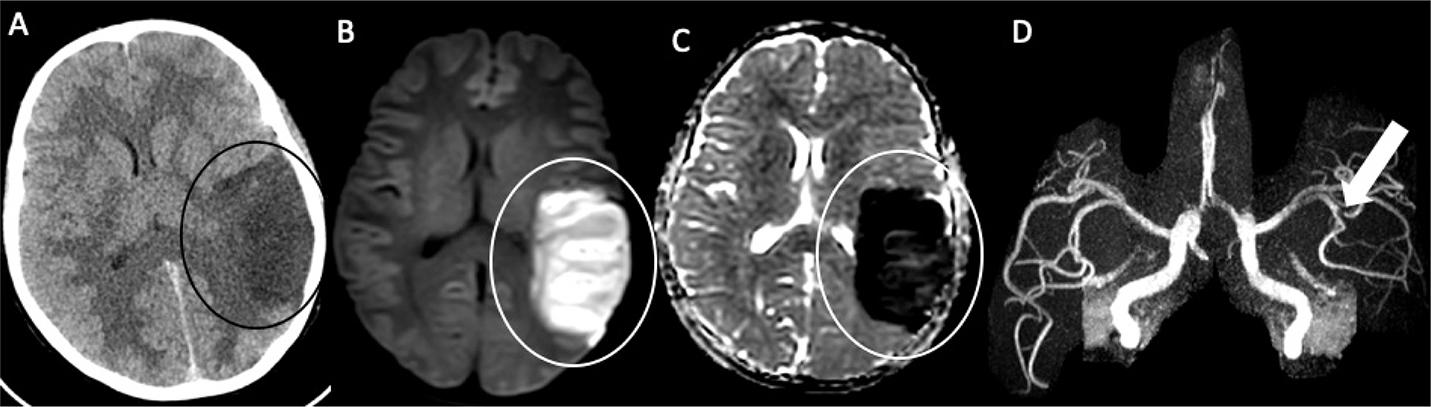

Fig 4

Figure 4. A 19-year-old female with a history of Down syndrome and repaired ASD and VSD. The patient presented with 2 days of aphasia, alerted mental status, and right upper quadrant field cut. Axial CT (A) demonstrates hypoattenuation with loss of gray-white differentiation in the left middle cerebral artery territory (black circle). DWI (B) and corresponding ADC (C) confirm acute left MCA territory infarct (white circle). MRA (D) demonstrates focal left MCA M2/M3 occlusion (arrow). She was found to be positive for Lupus anticoagulant.